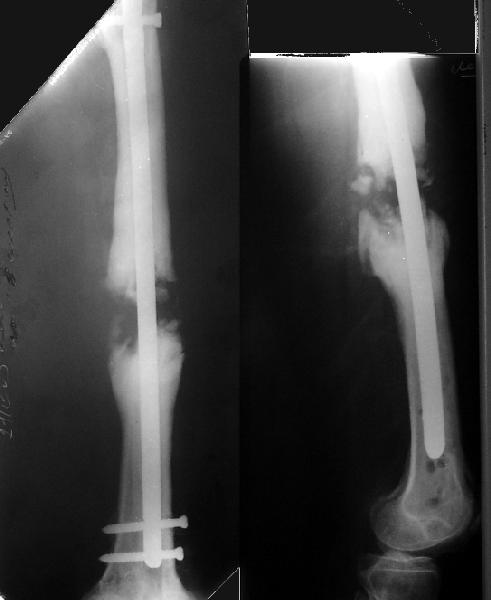

Стержень можно использовать и обычный потолще, но лучше бы с возможностью введения большего, чем два фронтальных, числа запирающих винтов.

Учитывая наличие этой мощной спайки, запереть можно сразу динамически.